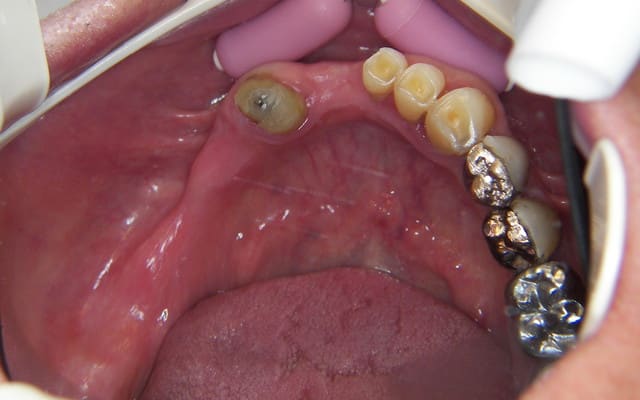

photos de la bouche au départ

100 4442r ro8hie - Eugenol

100 4473r hvl501 - Eugenol

100 4446 o2upvt - Eugenol